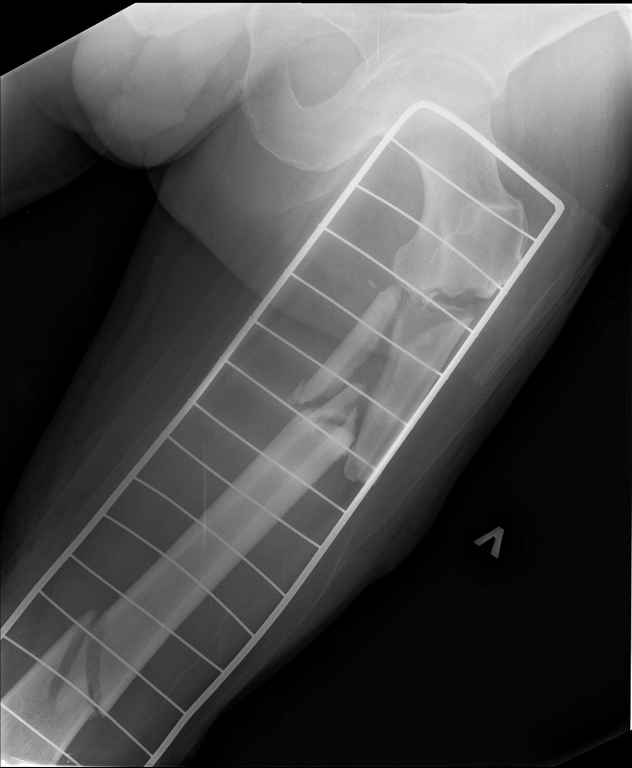

Ds: ТСТ. ЗЧМТ. СГМ. ЗТГК. О/фрагментарный перелом левого бедра. З/оскольчатый перелом с\3 левого плеча. Перелом левого локтевого отростка. З/перелом наружного мыщелка б/берцовой кости в/3 м/берцовой кости левой голени. при поступлении, ПХО раны левого бедра( рана 1х1см по наружной поверхности бедра в с/3) налажено скелетное вытяжение , и гипсовая лонгета на левую в/конечность. Находился в реанимации. 17.02.11 был прооперирован: БИОС левого плеча, о/синтез левого локтевого отростка по Веберу, БИОС левого бедра (длинная версия Fi-Can Sanatmetal диаметр 10мм), мыщелок голени трогать не стали. при остеосинтезе бедра возникли трудности при закрытй репозиции перелома в н/3, в связи с чем решили открыться внизу , отрепонировали без особого труда и выполнили блокирование во фронтальной плоскости 3-мя винтами + 1 винт спереди гвоздя (промазал). Убрал костодержатель, все нормально, контроль ЭОПом стояние отломков нормальное, зашились. На контрольной R-мме на утро выявлено вторичное смещение дистального отломка. Левая нога по сравнению со здоровой удлиннена до 2,5см( это за счет вальгусной установки гвоздя в проксимальном отделе, боялся свалиться на варус). Теперь думаем как поправить положение отломков в н/3, и зафиксировать так чтобы не съехало. Наше предложение расшиться в н/3 бедра, разблокироваться, перелом отрепонировать вновь и установить 1или 2отклоняющих винта в сагитальной плоскости, затем заблокироваться во фронтальной плоскости снова. Помогите советом, как выйти достойно из сложившейся ситуации. Заранее спасибо.